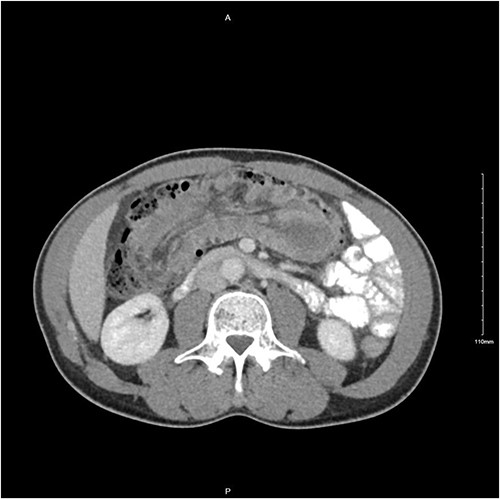

A 56-year-old male was diagnosed with a 4-day history of worsening, cramping left-sided lower abdominal pain and persistent vomiting. The patient had experienced intermittent bouts of similar pain in the previous few months; however, the sustained nature of the pain on this occasion prompted his presentation. Clinical examination elicited lower abdominal tenderness, most marked in the right para-umbilical region. He was an otherwise healthy patient, with no pertinent medical history. Initial investigations revealed a white cell count of 11.78 × 109/L with an associated mild neutrophilia of 9.29 × 109/L. His C-reactive protein was significantly elevated at 130 mg/L, with remaining haematological tests otherwise unremarkable. A computed tomography (CT) scan with intravenous contrast of the abdomen and pelvis was performed which identified a long segment (21 cm) of intussusception involving the distal small bowel, caecum and ascending colon and entirety of transverse colon, including mesentery (Fig. 1). A 5.5-cm hypodense mass was noted within the splenic flexure of the transverse colon which acted as a lead point for intussusception (Fig. 2). There was no pathological small bowel dilatation. Radiologically, the suggested differential diagnosis included gastrointestinal stromal tumour, carcinoid tumour, leiomyosarcoma, lymphoma or benign pathologies such as leiomyoma. The patient proceeded to theatre whereby a formal resection by means of extended right hemicolectomy and primary anastomosis was performed. Histological analysis demonstrated an ileal myxoma to be the causative pathology. The patient had an unremarkable post-operative course and was discharged well 1 week post-operatively.

Transverse CT image demonstrating long segment of small bowel telescoping towards splenic flexure of the colon.